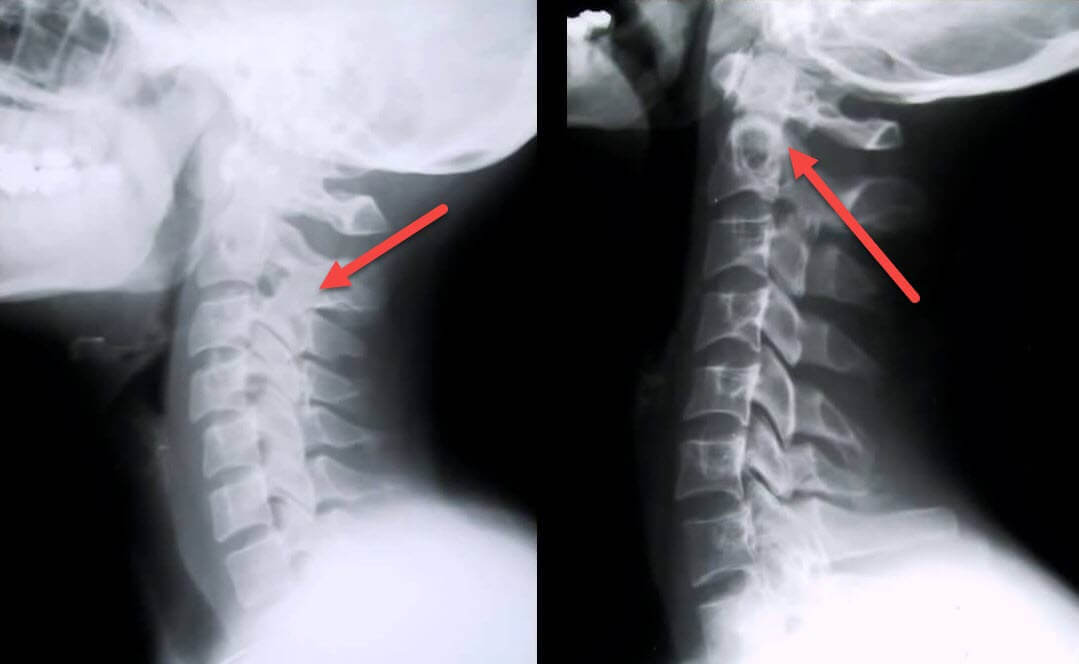

К кому обратиться при шейном остеохондрозе

Больному важно знать, к какому врачу можно обратиться при появлении боли в шейном отделе. Сначала необходимо записаться на прием к терапевту. Он выдает направление к неврологу, который занимается лечением остеохондроза. Он может направить на дополнительное исследование (рентгенография шейного отдела позвоночника, МРТ, КТ).

При отсутствии неврологической симптоматики и наличии грыж, этот врач может направить больного к вертебрологу, ортопеду травматологу. Если у пациента обнаруживается большая грыжа в шейном отделе и грубая неврологическая симптоматика, пациент может быть направлен к нейрохирургу для решения вопроса об оперативном лечении.

После обследования врачом и определения области боли врач может направить вас на рентген для более точной постановки диагноза.

Обычно при остеохондрозе обращаются к профильному врачу – неврологу, который производит осмотр, пальпирование и простукивание позвоночника с целью выявления места возникновения боли. После осмотра пациента врач данной специализации назначает полное обследование для определения формы и стадии поражения позвоночника и установления точного диагноза:

- Рентген показывает, какое место позвоночника подверглось дистрофическим изменениям и степень этого поражения, выявляет наличие смещенных дисков, образование наростов (остеофитов). Обычно делается в 2-х проекциях.

- МРТ и КТ проводится после рентгена для уточнения состояния межпозвоночного диска, выявления новообразований. Данные методы дорогостоящие, нет возможности применять их для всех пациентов.

Вне зависимости от того, идет ли пациент к неврологу, артрологу, вертебрологу или другому врачу, ему предстоит пройти обследования. На первом визите специалист определит на каком уровне расположен патологический очаг. Для этого он назначает МРТ, реже – КТ или рентгенотомографию шейного, грудного или пояснично-крестцового отдела позвоночника (или нескольких сразу).